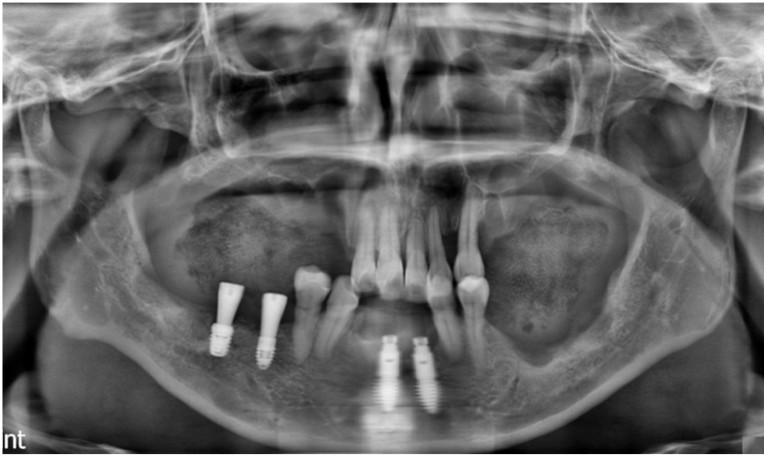

먼저 예후가 좋지 않은 치아들과

타 치과에서 식립 해 둔

아래턱 앞니 임플란트를

모두 제거하였으며,

아래턱 오른쪽 어금니 부위와

앞니에 먼저 임플란트 식립을

도와드렸는데요.

정확한 위치에

안정적으로 임플란트가 식립 된 것을

확인할 수 있었으며

한 달 반 뒤

아래턱 오른쪽 작은 어금니 부위에

임플란트 식립을 도와드렸으며,

큰 어금니 부위에는

잔존 잇몸뼈의 소실이 심한 상태라

바로 임플란트 식립을 진행하지 못하고

뼈이식을 도와드렸는데요.

그 후 정기적인 체크를 통해

오른쪽 위아래 임플란트는

식립해 둔 Fixture와

잇몸뼈가 단단히 결합이 된 것을 확인하고

최종 보철물 제작을 위한

본뜨기를 진행하였는데요.

왼쪽 위아래 임플란트 식립 후

4개월 체크에서

Fixture와 잇몸뼈가

단단히 결합되고

잘 아물고 있는 것을 확인한 뒤

인상채득을 진행하였으며,